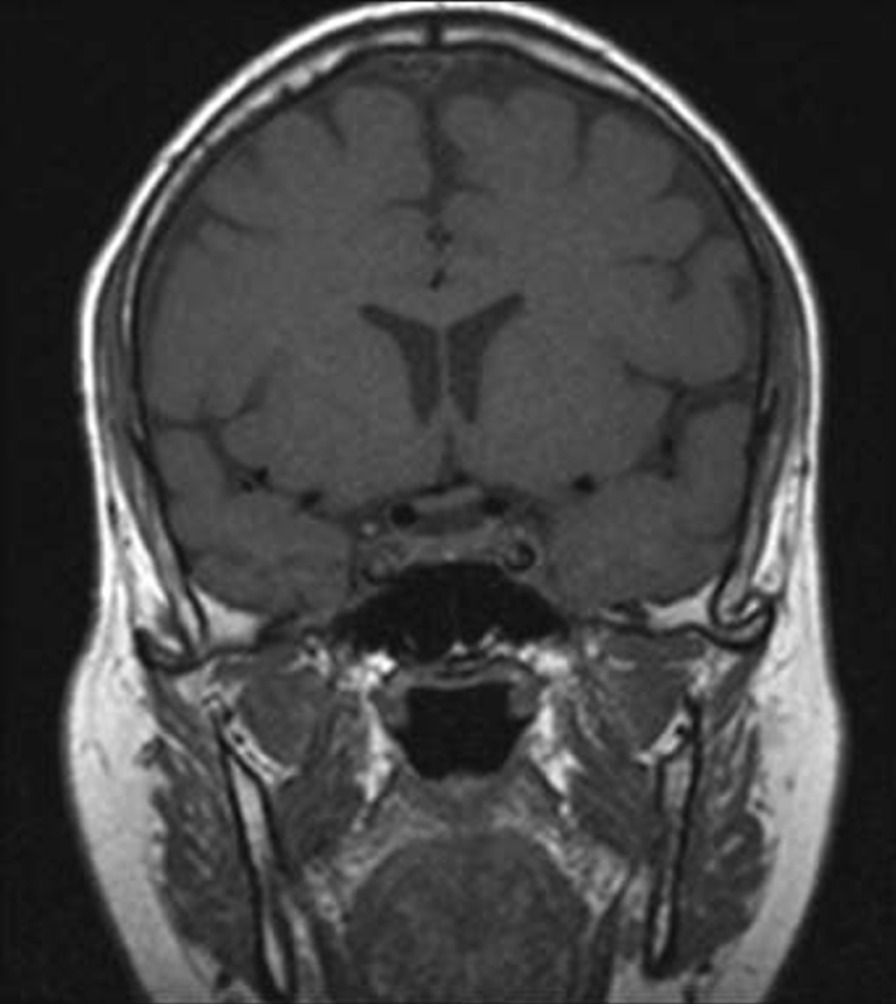

Fig. 2.

Pre-COVID-19 image of pituitary microadenoma. The image shows subtle asymmetry of both sides of the pituitary gland. The left side is slightly prominent, with a 3 × 3 × 2.5 mm faint ill-defined hypointense lesion (red arrow). Enhancement in the delay film shows no deviation of the pituitary stalk (microadenoma)